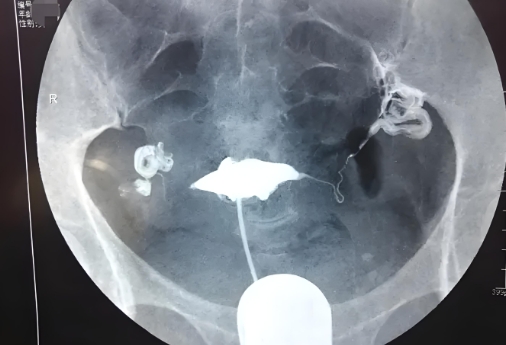

从检查的范围来看,腹部B超主要是通过探头在腹部皮肤上移动,在体表上观察子宫、卵巢、输卵管等器官的形态、大小、位置等情况。而阴超则是通过把探头插入到阴道内部来进行探测,可以更加详细地观察到子宫内膜、卵巢等器官的情况。

如果需要观察子宫内膜或者病变较小的卵巢肿块等情况,则建议选择阴超;

如果只需要了解一般情况下各器官的基本状态,则可以选择腹部B超。